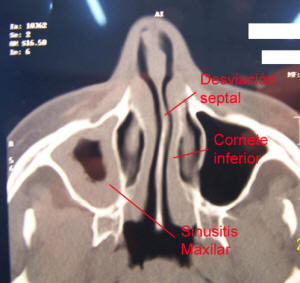

Causas de obstrucción nasal

Pueden ser causa de obstrucción nasal: rinitis viral, bacteriana o alérgica; sinusitis aguda, sinusitis crónica; agentes irritantes o contaminantes; causas hormonales, medicamentos locales; enfermedades autoinmunes; pólipos inflamatorios: poliposis rinosinusal, poliposis nasal recidivante; engrosamiento crónico de cornetes; desarrollo de adenoides; causas tumorales; alteraciones de la anatomía nasal por traumatismos o por trastornos durante el desarrollo; cornetes bullosos (muy desarrollados con aire en su interior); y otras causas.

Una de las causas mas frecuentes de obstrucción nasal es la desviación del tabique nasal ya sea porque a lo largo del desarrollo del macizo facial la anatomía de esta estructura se ha alterado con excesivo desarrollo para el marco existente. Otra posibilidad es el tabique nasal desviado producto de un traumatismo.

El tabique nasal desviado aumenta la resistencia al paso del aire; el flujo normal de aire se altera y compromete la fisiología normal de la mucosa nasal y de los senos paranasales, alterando las características del moco y de la función ciliar.

El septum nasal desviado puede comprimir o empujar a los cornetes hacia la pared externa de las fosas y estos a su vez, pueden bloquear la vía natural de drenaje de los senos paranasales (los orificios de ventilación de los senos paranasales).

Como consecuencia, el tabique nasal desviado (desviación del septum nasal) constituye un motivo bastante frecuente de bloqueo nasal (obstrucción nasal) y de sinusitis crónica.